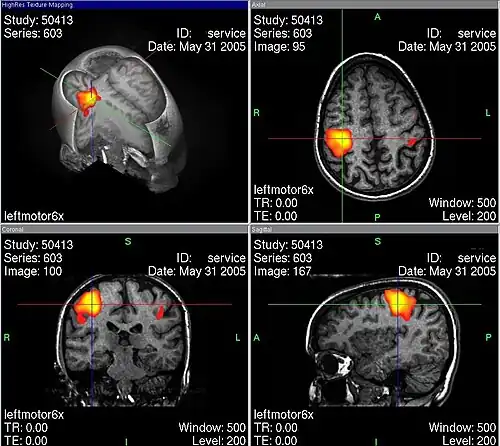

Eine neuere Methode ist die dreidimensionale Rekonstruktion von Magnetresonanztomographie-Aufnahmen nach Kontrastmittelgabe (MR-Angiographie). Diese verdrängt zunehmend die invasive Angiographie. Es existieren daneben qualitativ unterlegene MR-Sequenzen zur Gefäßbildgebung ohne Kontrastmittel (Time-of-flight-Magnetresonanzangiographie). Genauso ist auch mit der Computertomographie nach Kontrastmittelgabe eine Gefäßdarstellung möglich. Umschriebene Änderungen der Mikrozirkulation sind mit Positronen-Emissions-Tomographie, SPECT und mit einem speziellen (sauerstoffsättigungsgewichtetem) MR-Signal (BOLD-Kontrast) darstellbar. Optische Methoden stützen sich auf die Messung der Konzentrationsänderungen von Hämoglobin. Mit ihnen können nur oberflächennahe Blutflussänderungen gemessen werden.

Funktionelle MRT – stärker durchblutete Areale eingefärbt -